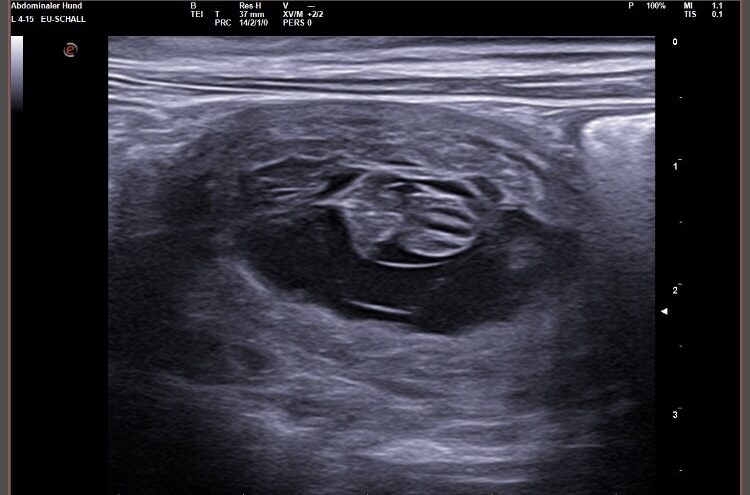

Wir waren erfolgreich und konnten Fruchtanlagen mit schlagenden Herzen sehen. Wir gehen zum aktuellen Zeitpunkt wieder von einem größeren Wurf aus. Daykos und Dorias Rendevouz war also sehr vielversprechend!

Hier zeigen wir euch einige der kleinen gefüllten Fruchtblasen mit Inhalt und schlagenden Herzen. Da wir kurz vor Ostern mit der Geburt rechnen, nennen wir sie „Ostereier“ 🙂